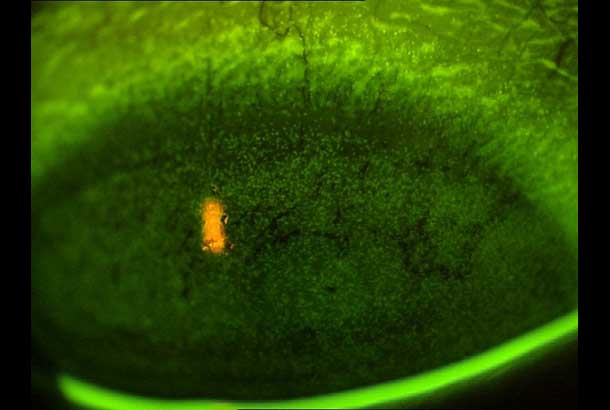

"name": "Vascularized Limbal Keratitis (VLK)",

"detail": "<h2>Symptoms</h2>\n\n<ul>\n\t<li>Patient may notice red area at limbus</li>\n\t<li>Slight stinging or irritation may be reported</li>\n</ul>\n\n<h2>Signs</h2>\n\n<ul>\n\t<li>Superficial vascularized lesion of the corneal periphery at the 3 and/or 9 o&rsquo;clock locations</li>\n\t<li>Wing shaped, raised lesion encroaching the cornea from the bulbar conjunctiva</li>\n</ul>\n\n<h2>Etiology</h2>\n\n<ul>\n\t<li>Sequellae to chronic inflammation in GP wearers</li>\n\t<li>Inadequate tear film and wetting result in punctate epithelial keratopathy</li>\n</ul>\n\n<h2>Prevalence</h2>\n\n<ul>\n\t<li>Rare</li>\n</ul>\n\n<h2>Differential Diagnosis</h2>\n\n<ul>\n\t<li>Pterygium (degenerative and hyperplastic condition in which the conjunctiva actively invades the cornea)</li>\n\t<li>See: <a href=\"/condition/63\">Hyperemia and Vascularization &ndash; Differential Diagnosis</a></li>\n</ul>\n\n<h2>Management</h2>\n\n<ul>\n\t<li>Eliminate 3 and 9 o&#39;clock staining through modification of the GP design</li>\n\t<li>Change to soft lenses, daily disposable or SiHy</li>\n\t<li>Use rewetting drops or reduce wearing time</li>\n</ul>",